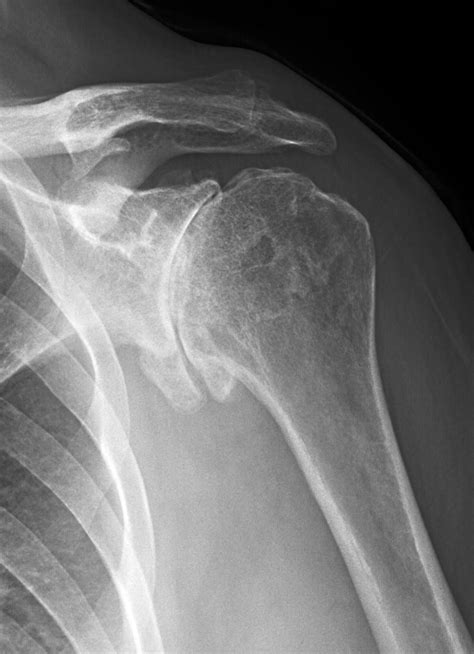

• Arthritis Assessment: It helps detect signs of osteoarthritis, such as narrowing of the joint space or bone spurs, which often cause chronic stiffness and pain.

Joint Space Narrowing Suggests potential osteoarthritis or cartilage wear.

Bone Spurs (Osteophytes) Common in aging joints; may cause impingement or pain.